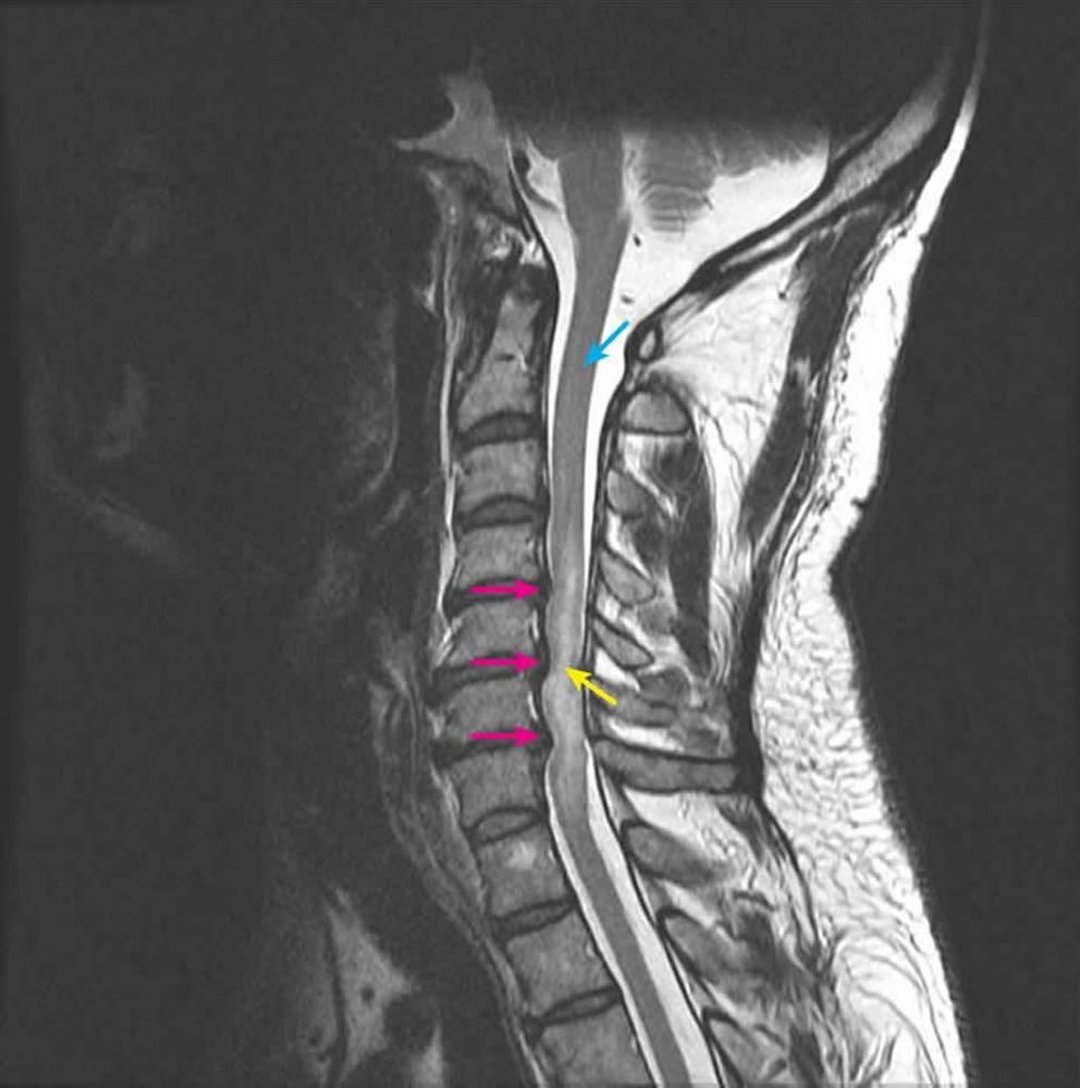

Source: pawnfidju.pages.dev Compression de la moelle épinière Compression de la moelle épinière Édition professionnelle , Ce prélèvement s'effectue soit au niveau du sternum soit au niveau de l'os iliaque Pour le faire, le professionnel de santé procède au prélèvement de moelle.